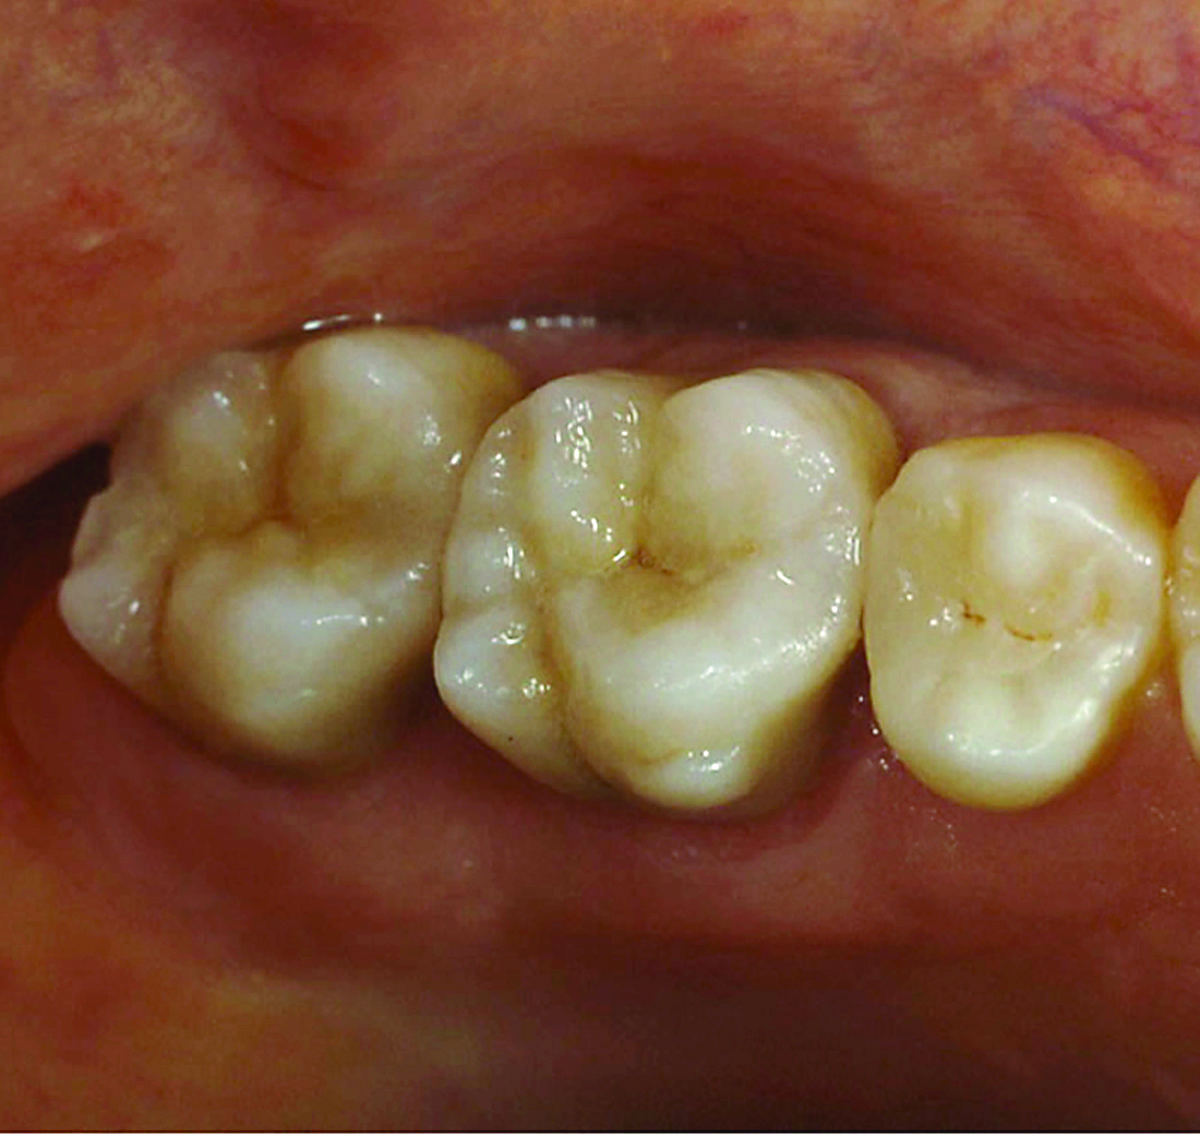

Fig 9. Preoperative view (Fig 9), preparation with composite block-out restoration (Fig 10), and final cementation of CL-IIb material (Fig 11) (final ceramic contour and stain by Steve Lee, CDT, MDC).

Figure 9

Fig 10. Preoperative view (Fig 9), preparation with composite block-out restoration (Fig 10), and final cementation of CL-IIb material (Fig 11) (final ceramic contour and stain by Steve Lee, CDT, MDC).

Figure 10

Fig 11. Preoperative view (Fig 9), preparation with composite block-out restoration (Fig 10), and final cementation of CL-IIb material (Fig 11) (final ceramic contour and stain by Steve Lee, CDT, MDC).

Figure 11

An example of this material subcategory is lithium disilicate (eg, IPS e.max®, Ivoclar Vivadent), a glass ceramic material composed of silica, lithium dioxide, alumina, potassium oxide, and phosphorous pentoxide. After the crystalline component has reached optimal growth through the manufacturing process, it is pulverized into powder and processed through a variety of different techniques.22 Lithium disilicate is indicated for the same clinical situations as other glass ceramics; however, when fabricated to a full-contour, monolithic restoration and seated with resin cement, it is also appropriate for higher stress situations, such as those requiring full crowns, even on molars (Figure 9 through Figure 11).

Restorations fabricated from this material subcategory demonstrate high strength, fracture resistance, and natural-looking esthetics,23 yielding a versatile and strong alternative for a wider variety of indications. They are indicated when higher risks are involved (eg, less than 50% enamel remains on the tooth, less than 50% of the bonded substrate is enamel, and/or when 30% or more of the margin is in dentin).

Due to the material's glass properties, adhesive bonding is recommended. However, bonding to dentin results in less predictable restorations due to dentin's flexibility; restorations bonded to enamel are much more predictable, given enamel's significant stiffness compared to dentin.19